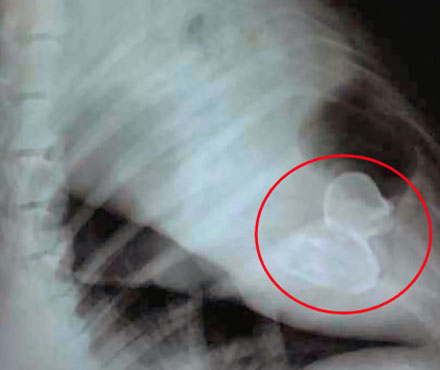

According to the Veterinary Pet Insurance Company (in the US), policyholders spent almost $3 million treating cats and dogs that ingested foreign objects in 2010!!

1. My dog had to have a rubber duck surgically removed from his intestines, it almost killed him 😦